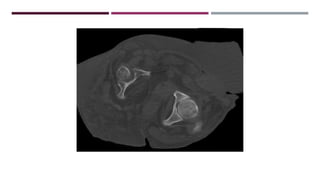

MASA SÓLIDO/QUISTICA

MESENTERIO/PERITONEO

LESION FOCAL PARED

ABDOMINAL

CALCIFICACION ESPLÉNICA